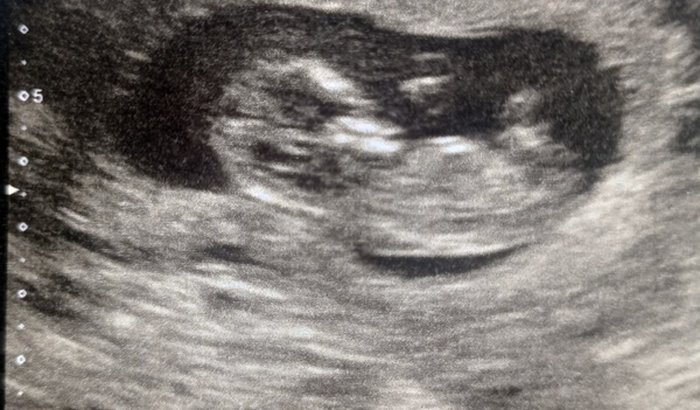

Me chamo ana paula estou gestante de 4meses 21 semanas e estou em uma gravidez com complicação, e muitos problemas de saúde,devido isso minha mfica pediu muitos exames porem são muitoa exames é uma delas eum ultra-som qe cuata cerca 600 $$ e fora os outros exames porem tanto eu quanto meu companheiro estamos desempregados

E uma gravidez de risco seguidas d muitas dores ,faltas de ar correndo risco do meu bebê nascer ate mesmo antes!